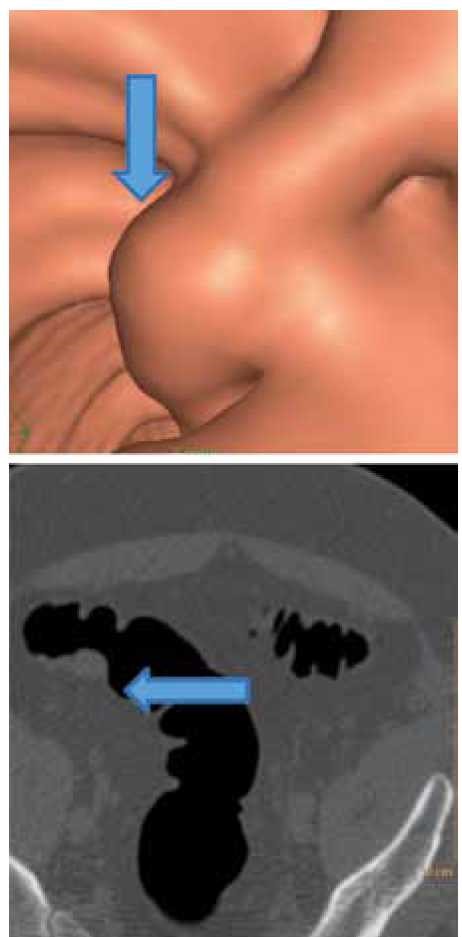

המראה בקולונוסקופיה וירטואלית (משמאל) לעומת קולונוסקופיה רגילה

פענוח הבדיקה מבוצע על ידי רדיולוגים מיומנים באמצעות תוכנה ייעודית. הפענוח כולל בחינה של החתכים הרוחביים הרגילים של בדיקת CT וכן ניווט וירטואלי בחלל המעי הגס. ניווט זה מאפשר לדמות קולונוסקופיה רגילה (מכאן השם 'קולונוסקופיה וירטואלית׳), וניתן לראות בו פוליפים או מסות, לקבוע את המרחק מהאנוס, ובהמשך לכוון, במידת הצורך, את הגסטרואנטרולוג כאשר יתבקש להסיר את הפוליפים שהתגלו (תמונה מספר 1).